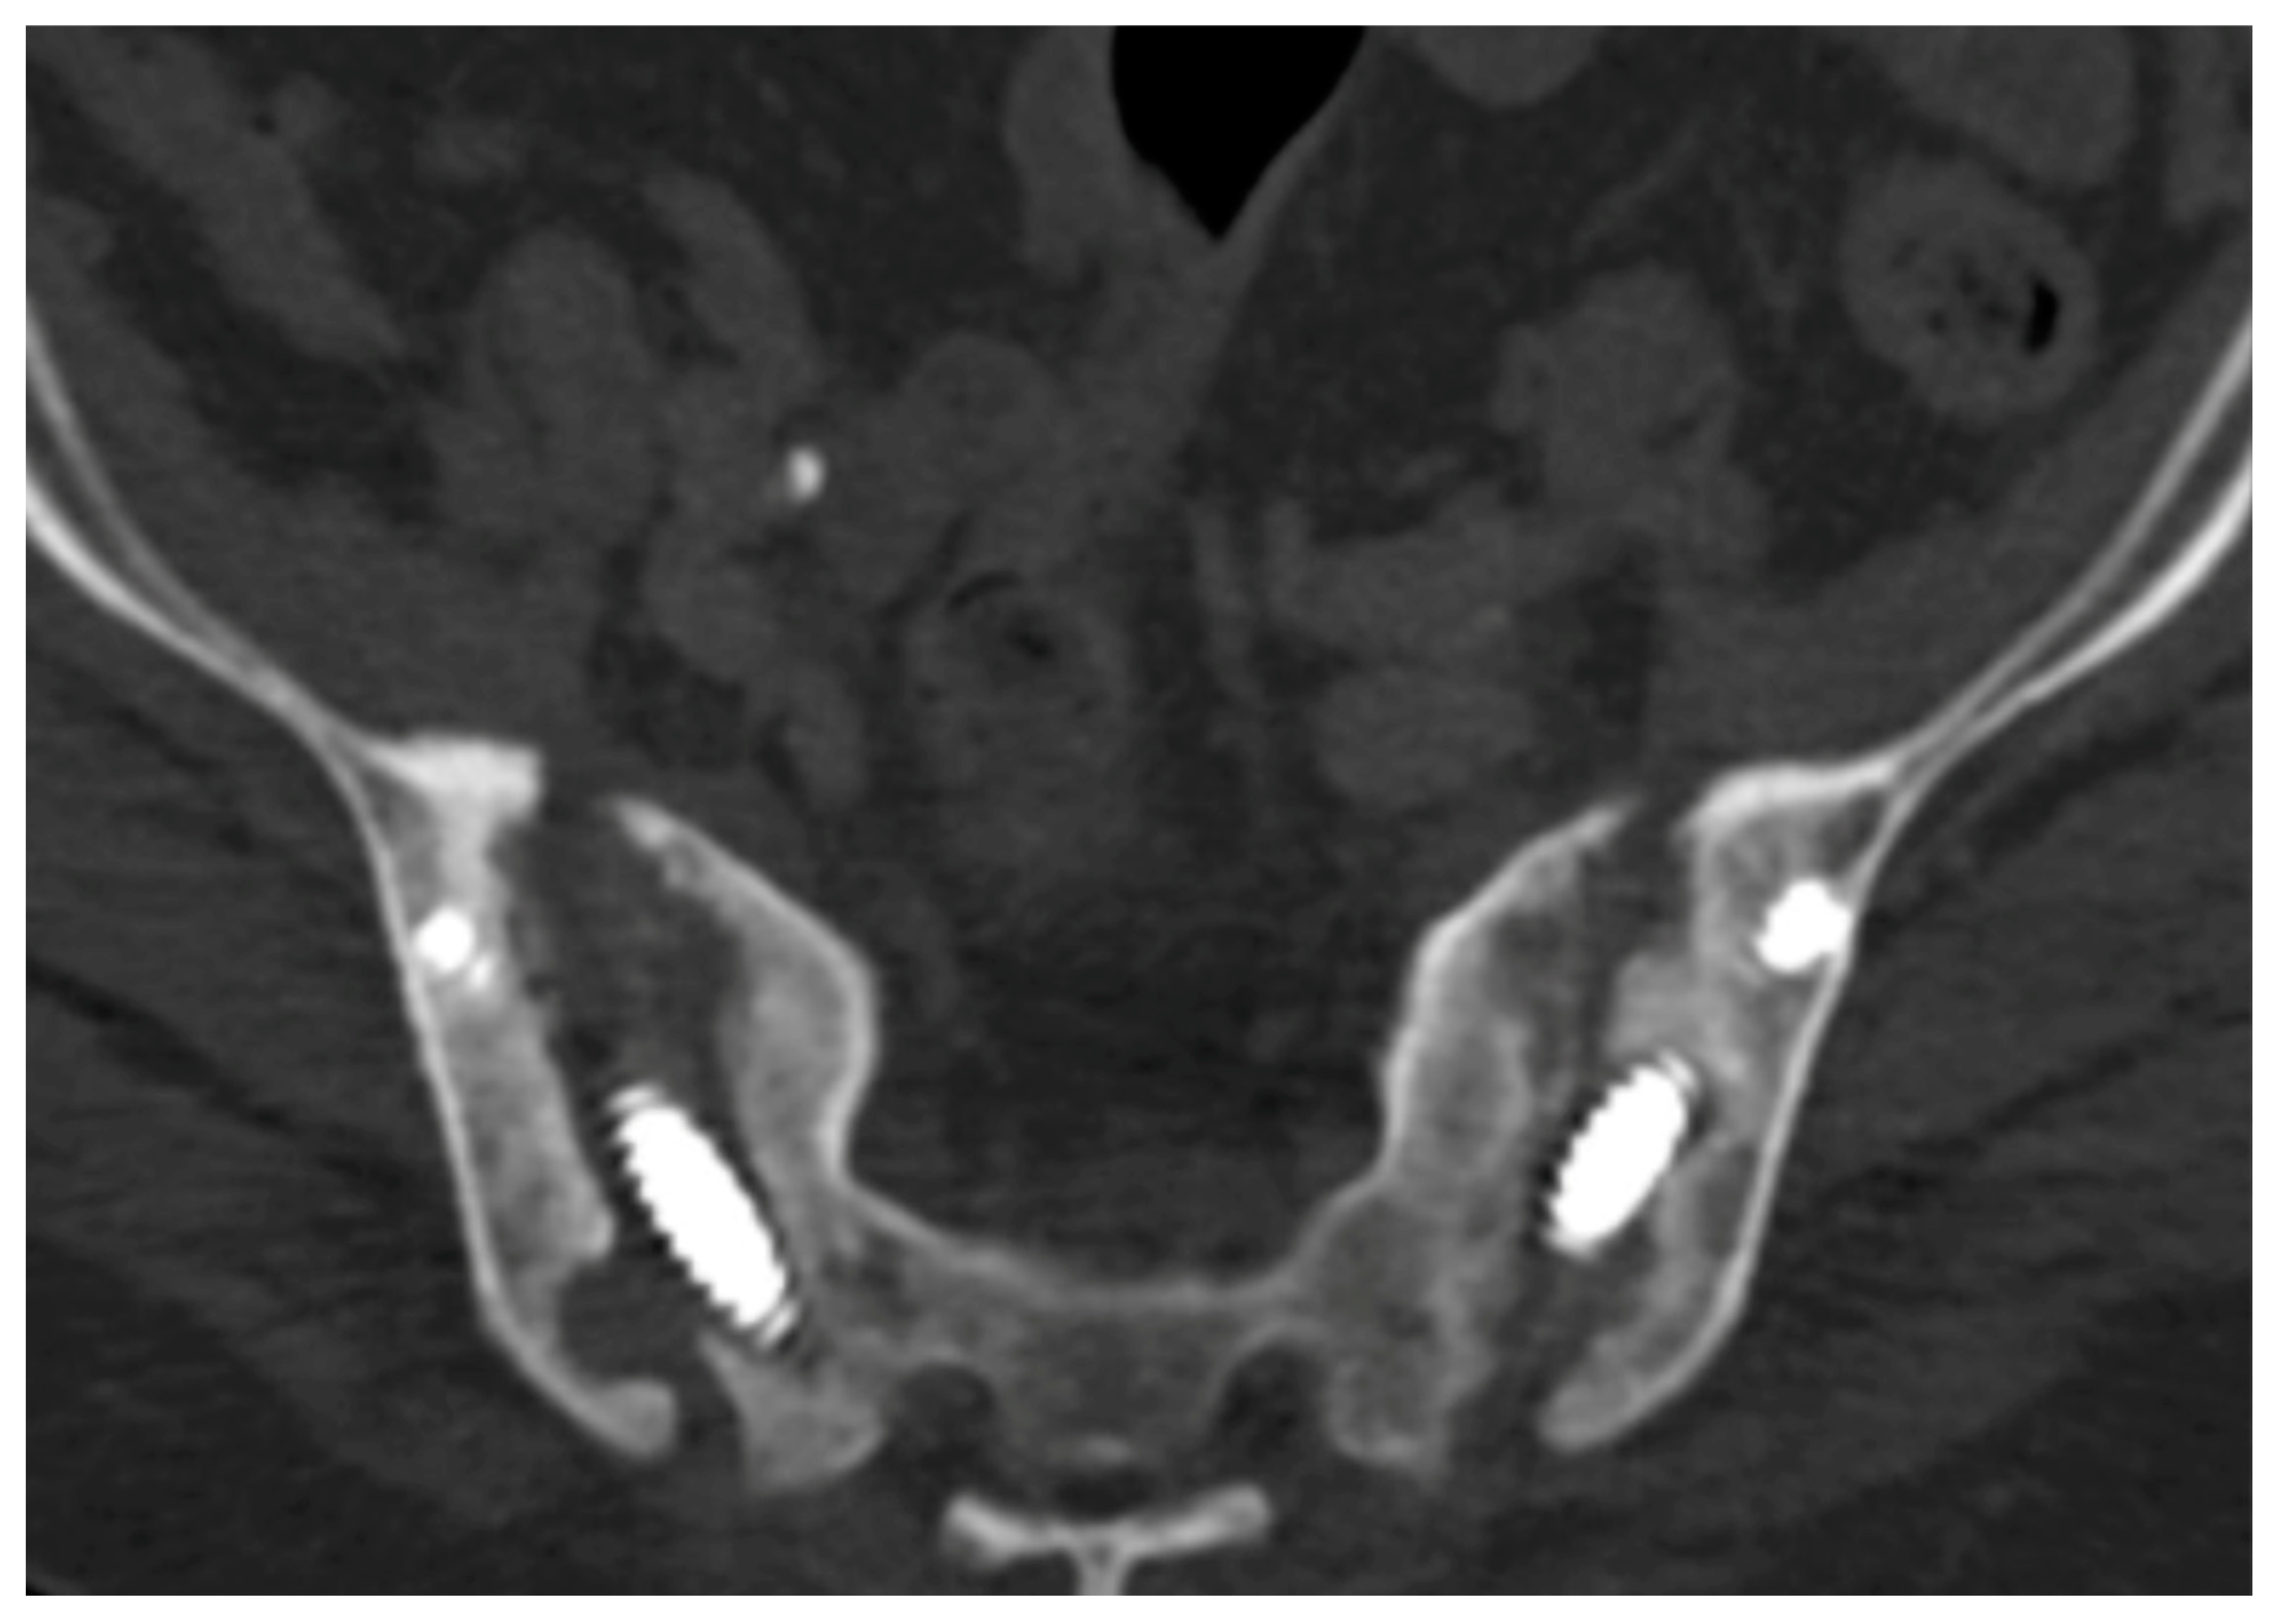

6. Spinopelvic Fixation Percutaneous Technique

7. Tran-Sacral Percutaneous Technique